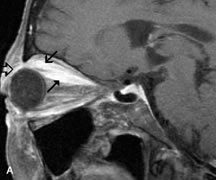

Cavernous hemangiomas appear as well-circumscribed, smooth, usually intraconal masses that are isointense to muscle on T1-weighted images and hyperintense on T2-weighted images (Fig. 12). Patchy early enhancement is typically followed by diffuse, more homogeneous enhancement.39 The internal architecture of the mass, including septation and internal vasculature, may often be appreciated with high-quality orbital imaging.40

Fig. 12. A. T1- and (B) T2-weighted MR scans demonstrate a well-circumscribed intraconal mass causing severe optic nerve displacement. These lesions are usually intermediate in signal intensity on T1-weighted scans and very hyperintense on T2-weighted Images. C and D. Postcontrast fat-suppressed T1-weighted scans demonstrate characteristic patchy intense enhancement that becomes more complete from the initial postcontrast scan (C) to a more delayed scan (D).